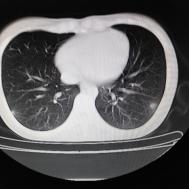

[影像描述]

两肺内及胸膜下多发斑片状高密度影,部分病灶密度较淡,部分实变,边缘可见渗出改变。